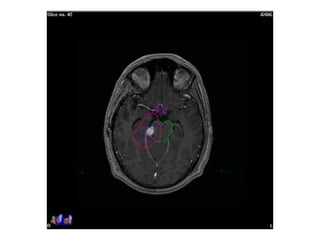

RT planning: meningioma

GTV/CTV = residual tumour / tumour bed for gr II / gr III

CTV = 5 mm for benign meningiomas

2 - 3 cms for high grade meningiomas / HPC

PTV = 2mm for SRT

5mm for 3DCRT

All normal structures contoured

Dosage:

Gr-I:

54Gy/30# conformal RT

25Gy/5# / 13Gy/1#

Gr II & III meningioma:

60Gy/30#/6wks

Conformal RT

Grade I Grade II/III

Tharmoplastic mask

CT scan with contrast- 3 mm slice

MRI scan with T1 contrast & T2 flair is a must